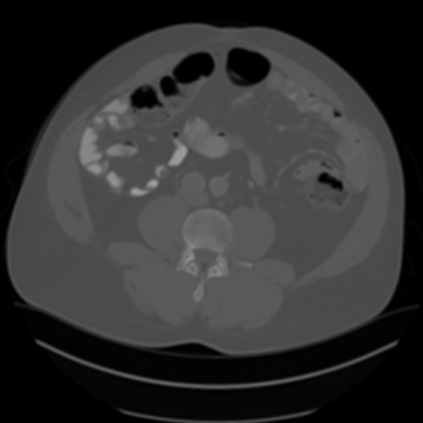

Sparse-view computed tomography (CT) -- using a small number of projections for tomographic reconstruction -- enables much lower radiation dose to patients and accelerated data acquisition. The reconstructed images, however, suffer from strong artifacts, greatly limiting their diagnostic value. Current trends for sparse-view CT turn to the raw data for better information recovery. The resultant dual-domain methods, nonetheless, suffer from secondary artifacts, especially in ultra-sparse view scenarios, and their generalization to other scanners/protocols is greatly limited. A crucial question arises: have the image post-processing methods reached the limit? Our answer is not yet. In this paper, we stick to image post-processing methods due to great flexibility and propose global representation (GloRe) distillation framework for sparse-view CT, termed GloReDi. First, we propose to learn GloRe with Fourier convolution, so each element in GloRe has an image-wide receptive field. Second, unlike methods that only use the full-view images for supervision, we propose to distill GloRe from intermediate-view reconstructed images that are readily available but not explored in previous literature. The success of GloRe distillation is attributed to two key components: representation directional distillation to align the GloRe directions, and band-pass-specific contrastive distillation to gain clinically important details. Extensive experiments demonstrate the superiority of the proposed GloReDi over the state-of-the-art methods, including dual-domain ones. The source code is available at https://github.com/longzilicart/GloReDi.